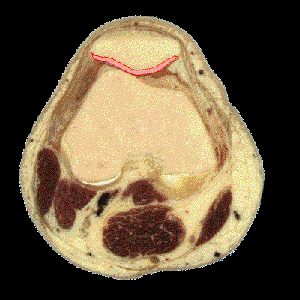

CARTILAGO ROTULIANODescripción: La parte posterior de la rótula está recubierta por la capa más gruesa de cartílago hialino que existe en el cuerpo. Origen: Las tres cuartas partes superiores de la rótula están cubiertas por cartílago hialino de 5 a 6 mm de grueso. La cuarta parte inferior de la rótula es superficie no-articular y no está recubierta por cartílago. Función: Amortiguación de los choques producidos durante las flexiones. El reblandecimiento del cartílago rotuliano (condromalacia rotuliana) es una cause frecuente del dolor de rodilla.